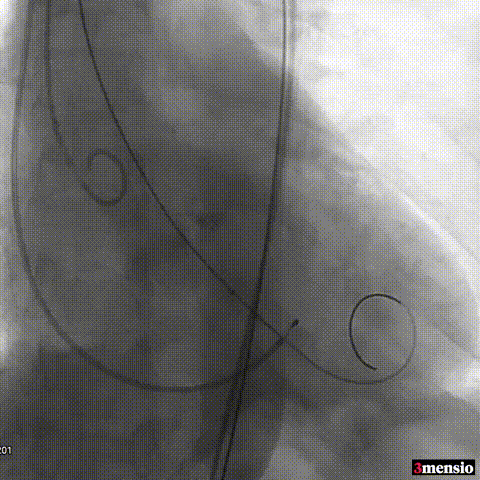

术后即刻评估:

图片

术后压差从66mmHg降至2mmHg,瓣膜正常工作,患者血流动力学即刻得到改善。